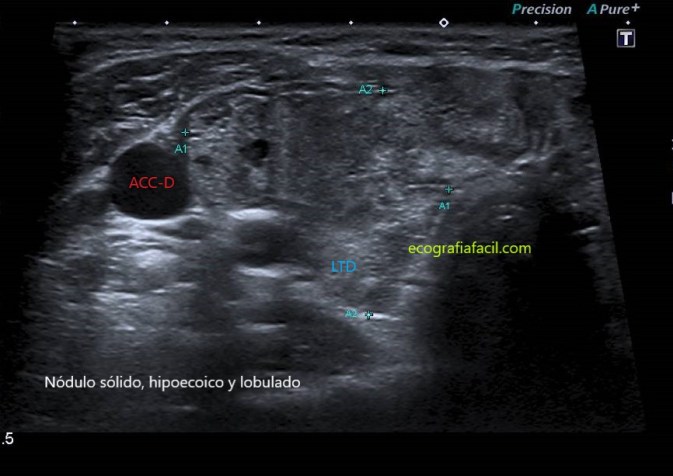

LOBULADO:

TI-RADS 4

Moderadamente sospechosa de malignidad (entre el 5% y el 80%)

COMPOSICIÓN:Sólida                            2

ECOGENICIDAD: Hipoecoica                  2

FORMA: Más ancho que largo                0

MARGEN: Lobulado                                2

NO FOCOS ECOGÉNICOS:                        0

6 puntos